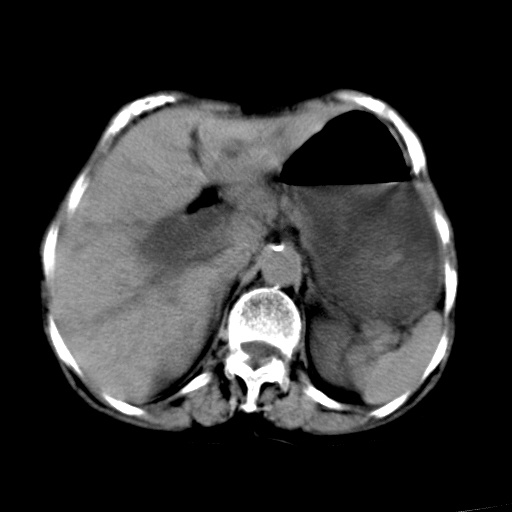

以下是引用杀毒软件在2009-3-4 17:38:00的发言:[br]为何没有喝照影剂呀? 胆总管及肝内胆管扩张,增强吧。[br][br]考虑-----十二指肠占位----建议----十二指肠镜检查[br][br]

以下是引用jiangjing在2009-3-4 17:45:00的发言:[br]低位胆道梗阻。十二指肠降段局部管壁增厚。扫描效果不理想,建议ct增强及ercp。

以下是引用杀毒软件在2009-3-4 17:38:00的发言:[br]为何没有喝照影剂呀? 胆总管及肝内胆管扩张,。增强吧。[br][br]考虑-----十二指肠占位----建议----十二指肠镜检查[br][br][br][br][本贴已被 杀毒软件 于 2009-3-4 17:56:38 修改过]